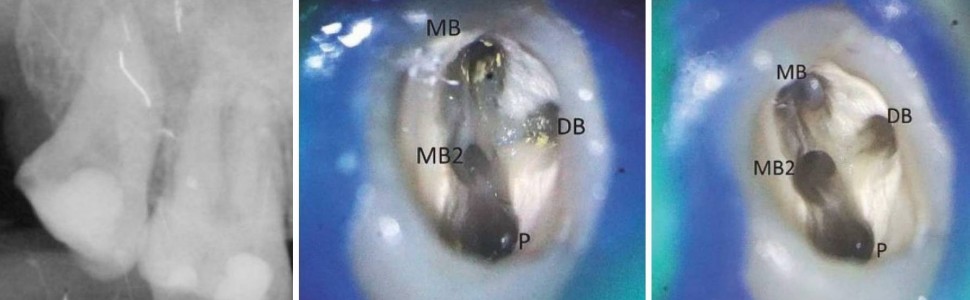

Jednym z najważniejszych etapów leczenia endodontycznego jest opracowanie kanału korzeniowego. Szczególnym wyzwaniem w codziennej praktyce są zęby o złożonej budowie systemu kanałowego. W takich przypadkach konieczne jest zastosowanie odpowiedniego sprzętu, m.in. powiększenie pola zabiegowego z użyciem mikroskopu czy też wykorzystanie narzędzi ultradźwiękowych. W pracy przedstawiono opis dwóch przypadków leczenia endodontycznego trzecich zębów trzonowych.

One of the most important stages of endodontic treatment is the preparation of the root canal. A particular challenge in everyday practice are teeth with a complex system of canals. In such cases it is essential to use the appropriate equipment, which includes enlargement of the surgical field, with among others, the use of the microscope or also using ultrasonic equipment. The study presented a description of two cases of endodontic treatment of third mandibular molars.

Przypadek 1

Opracowanie i odpowiednie ukształtowanie kanału korzeniowego stanowi jeden z najważniejszych etapów leczenia endodontycznego. Właściwe poszerzenie kanału zapewnia jego optymalną irygację i późniejsze szczelne wypełnienie (1). Opracowanie kanałów prostych nie sprawia wielu problemów. Pojawiają się one w przypadku występowania krzywizn czy złożonej budowy systemu kanałowego (2). W trudnych przypadkach jest konieczne zastosowanie odpowiedniego sprzętu, m.in. powiększenie pola zabiegowego z użyciem mikroskopu czy wykorzystanie narzędzi ultradźwiękowych. Do opracowania kanałów o znacznym stopniu zakrzywienia częściej stosuje się wykonane ze stopu niklowo‑tytanowego narzędzia ręczne lub maszynowe (3). Dzięki większej giętkości, w porównaniu z narzędziami ze stali nierdzewnej, łatwiej dopasowują się one do przebiegu opracowywanego kanału, a praca z ich wykorzystaniem skutkuje mniejszym ryzkiem powstania błędów jatrogennych (4, 5). Ze względu na skrócenie czasu pracy operatora szczególnym uznaniem lekarzy dentystów cieszą się niklowo-tytanowe narzędzia rotacyjne.